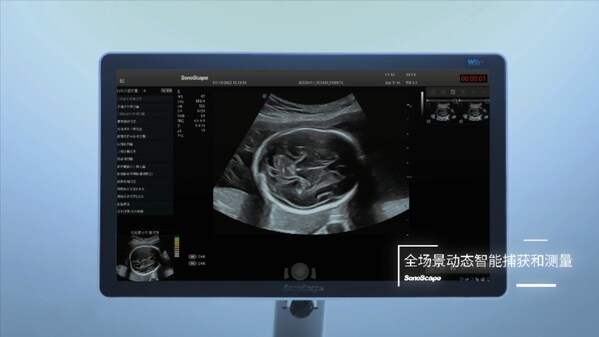

作為國(guó)內(nèi)首個(gè)獲批的產(chǎn)前超聲切面智能輔助識(shí)別與測(cè)量功能,鳳眼?S-Fetus®深度融合了超聲技術(shù)與人工智能,首個(gè)實(shí)現(xiàn)"全流程、全場(chǎng)景產(chǎn)篩智能化",讓開(kāi)立超聲成為全球首個(gè)具備切面自動(dòng)抓取、測(cè)量分析、超聲質(zhì)量控制的"整機(jī)智能",將積極推動(dòng)產(chǎn)前超聲智能化轉(zhuǎn)型的進(jìn)程。

鳳眼?S-Fetus®的問(wèn)世帶來(lái)了前所未有的變革。作為國(guó)內(nèi)首個(gè)基于深度學(xué)習(xí)的產(chǎn)科超聲智能檢測(cè)技術(shù),鳳眼?S-Fetus®也是全球首款基于動(dòng)態(tài)圖像對(duì)標(biāo)準(zhǔn)切面自動(dòng)抓取的人工智能技術(shù),能夠?qū)Τ晥D像中的組織結(jié)構(gòu)進(jìn)行實(shí)時(shí)檢測(cè),自動(dòng)抓取標(biāo)準(zhǔn)切面并進(jìn)行自動(dòng)測(cè)量,并實(shí)現(xiàn)了檢查過(guò)程中的實(shí)時(shí)質(zhì)控,顯著提高了產(chǎn)前超聲檢查的效率和準(zhǔn)確性。

鳳眼?S-Fetus®支持精確的胎兒生物學(xué)測(cè)量,并自動(dòng)發(fā)送至報(bào)告,使醫(yī)生的工作流更加順暢,有效節(jié)約了掃查時(shí)間,讓醫(yī)生更專(zhuān)注于患者的診斷與治療。"全流程、全場(chǎng)景產(chǎn)篩智能化"將有力為醫(yī)生的工作負(fù)荷做"減法",同時(shí)有助于提升基層醫(yī)生和年輕醫(yī)生獲取標(biāo)準(zhǔn)切面的能力,推動(dòng)產(chǎn)前超聲技術(shù)的智能化、高效化發(fā)展,加速超聲行業(yè)的技術(shù)創(chuàng)新進(jìn)程。